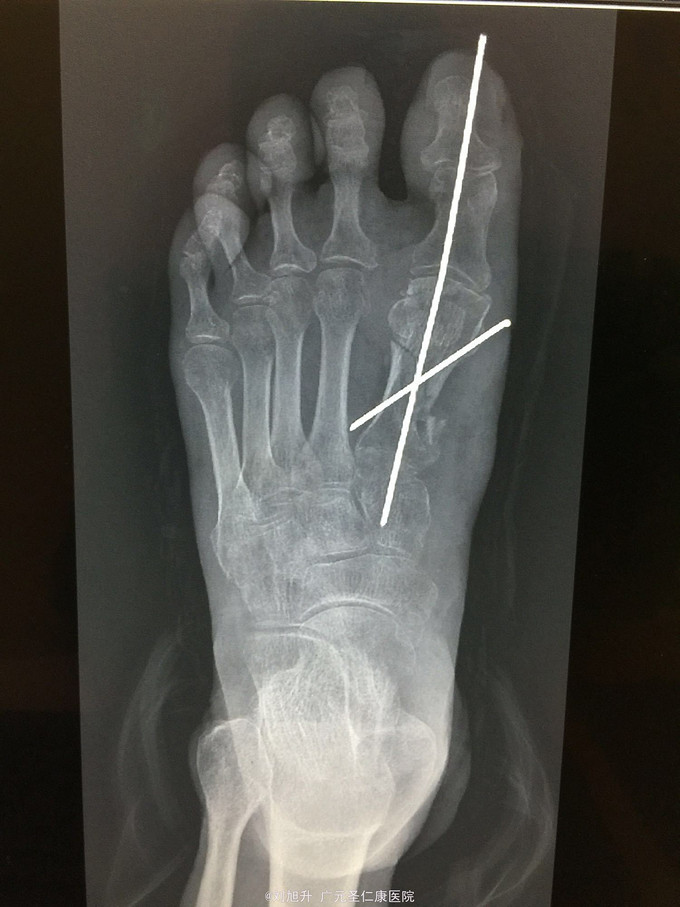

左足背砸伤

患者,男,61岁,因左足背重物砸伤5小时入院